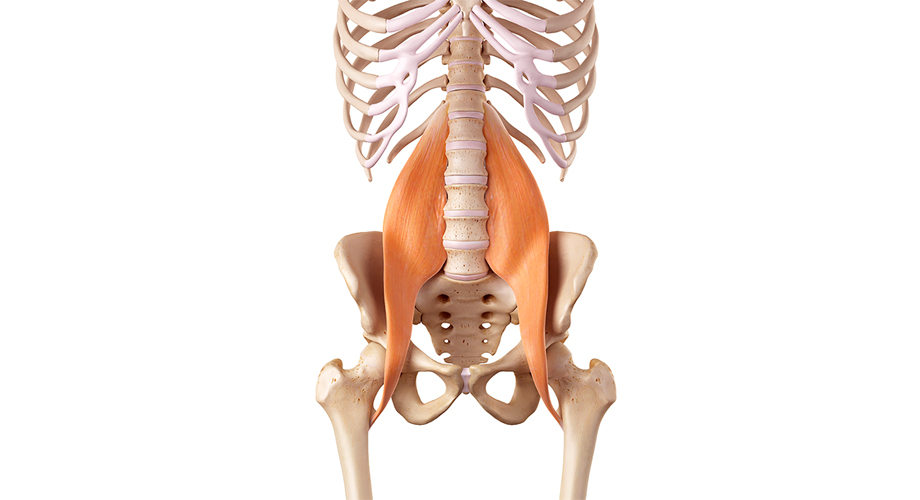

어떤 경우에는 허리 디스크로 인해 해당 부위의 근육이 약해질 수 있습니다. 이러한 근력 약화는 허리 디스크의 위치에 따라 다리나 팔에서 눈에 띄게 나타날 수 있습니다.

이는 조정력, 안정성, 특정 동작이나 작업 수행 능력에 영향을 미칠 수 있습니다.